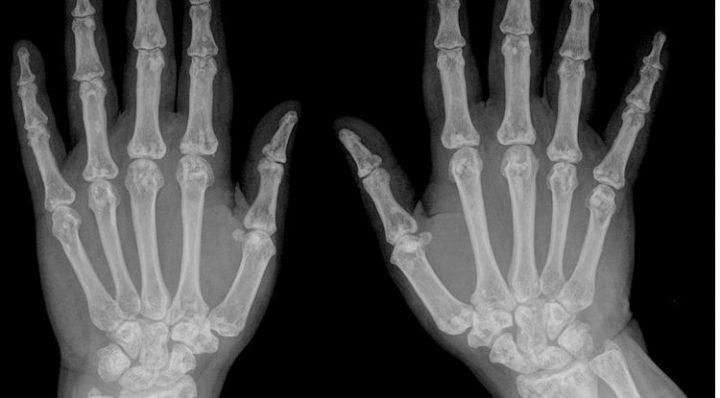

Die Medizin ist nicht in der Lage, das Alter „festzustellen“. ExpertInnen sind sich einig, dass nur eine grobe Schätzung mit einer Streubreite von mehreren Jahren möglich ist. Der Beweis, dass eine Person volljährig ist, lässt sich auch durch bildgebende Verfahren nicht mit der geforderten „an Sicherheit grenzenden Wahrscheinlichkeit“ erbringen. In der Praxis besteht daher ein erhebliches Risiko, dass Minderjährige durch die fehleranfällige Altersdiagnostik fälschlich zu Erwachsenen erklärt werden.

Die Zentrale Ethikkommission bei der Bundesärztekammer hat im September 2016 empfohlen, bis auf weiteres Röntgen- und Genitaluntersuchungen zum Zwecke der Altersschätzung abzulehnen, ebenso die Deutsche Akademie für Kinder- und Jugendmedizin. Die European Academy of Pediatrics empfiehlt seit 2015 allen Kinder- und Jugendärzten dringend, „nicht am Prozess der Altersfestsetzung von Asylbewerbern teilzunehmen, die angeben minderjährig zu sein“, und „diese Auffassung an alle anderen Ärzte weiterzugeben.“